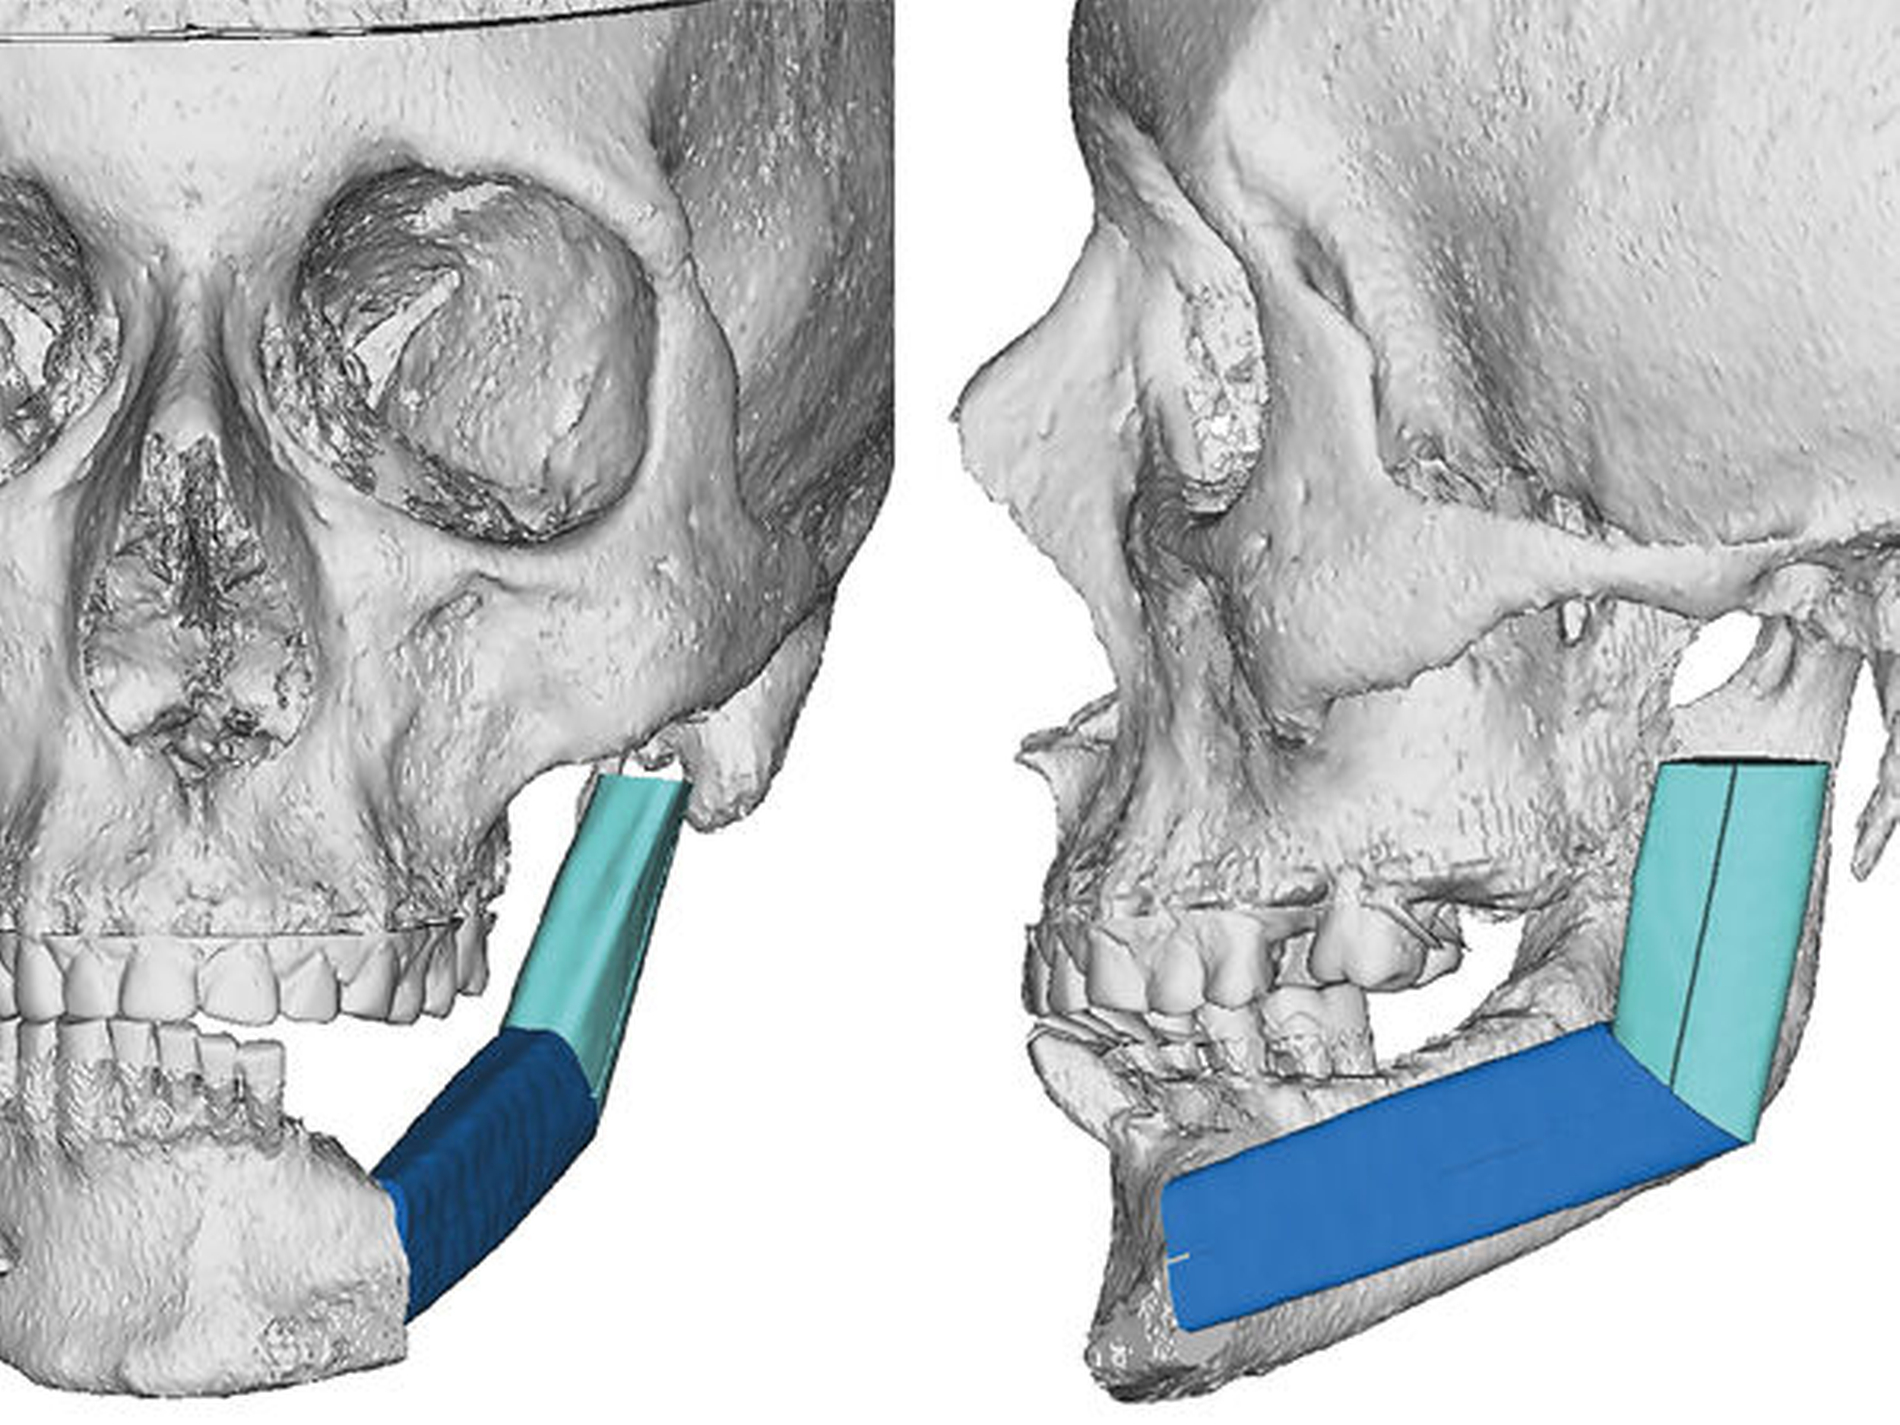

Die neue Okklusion wird postoperativ mittels intermaxillärem Splint gesichert (Abbildung 4). In den Folgeschritten werden die Resektionsgrenzen festgelegt und die notwendigen Fibulasegmente angepasst (Abbildung 5).

Die alloplastische Fossakomponente wird in der ehemaligen Fossa articularis platziert und am Arcus zygomaticus mit Schrauben fixiert. Bei dem BIOMET System wird der Rotationspunkt auf der Translationsbahn des natürlichen Kondylus nach kaudal gelegt, um die natürlichen translatorischen Bewegungen zu imitieren und die interinzisale Öffnung zu vergrößern [van Loon et al., 1999; van Loon et al., 2000]. In dem Plattendesign ist der Kondylus integriert, so dass hier keine Schwachstelle durch Schraubverbindungen entsteht (Abbildung 6).

Die zur Konstruktion der TEP konstruierten Teile, wie das PSI, die Fossa und Schablonen wurden durch Firma Biomet Microfix Inc. (Jacksonville, Florida, USA; [Vertrieb: Zimmer Biomet Deutschland GmbH]) hergestellt. Die Platte besteht aus einer Titan-Aluminium-Vanadium-Legierung, der Fossaanteil aus ultrahochmolekularem Polyethylen (UHMWE-PE) (Abbildung 7).